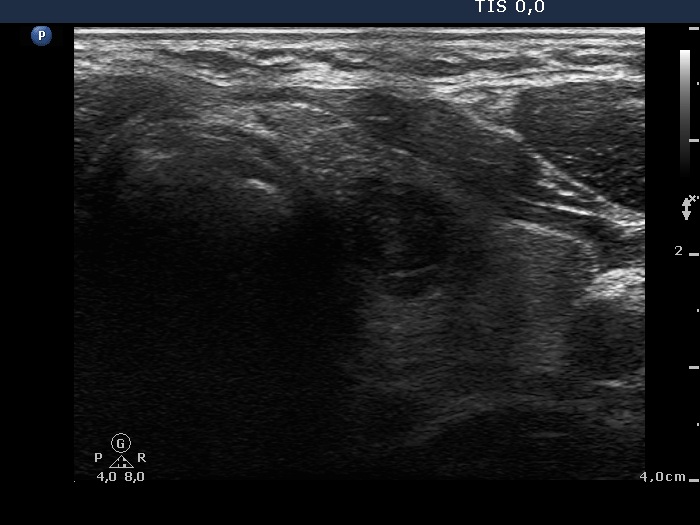

Second examination 7 years later (second row of images):

Clinical presentation. In the past 7 years, the patient had no complaints and therefore did not come to the proposed checkup either. Now he felt it was time to do an investigation.

Functional state: subclinical hypothyroidism with TSH 5.82 mIU/L, aTPO 98 U/mL.

Palpation: a hard nodule in the left lobe.

Ultrasonography. The presentation of the thyroid was essentially the same as 7 years ago. The only discrepancy was the lesion in the left lobe. Firstly, the size of the lesion have substantially increased to 25x18x25 mm (width, depth, and length, respectively), the volume was 5.89 mL which means that the volume became almost 8-times larger. Secondly, it was no more question whether the lesion was a pathological nodule or not. It turned out that this lesion is clearly a pathological nodule. Thirdly, in contrast to the former examination, the nodule has numerous microcalcifications and showed a clearly irregular, lobulated margins.

Aspiration cytology resulted in suspicion of papillary cancer.

Total thyroidectomy was performed, histopathology disclosed a T2 papillary cancer and Hashimoto's thyroiditis.